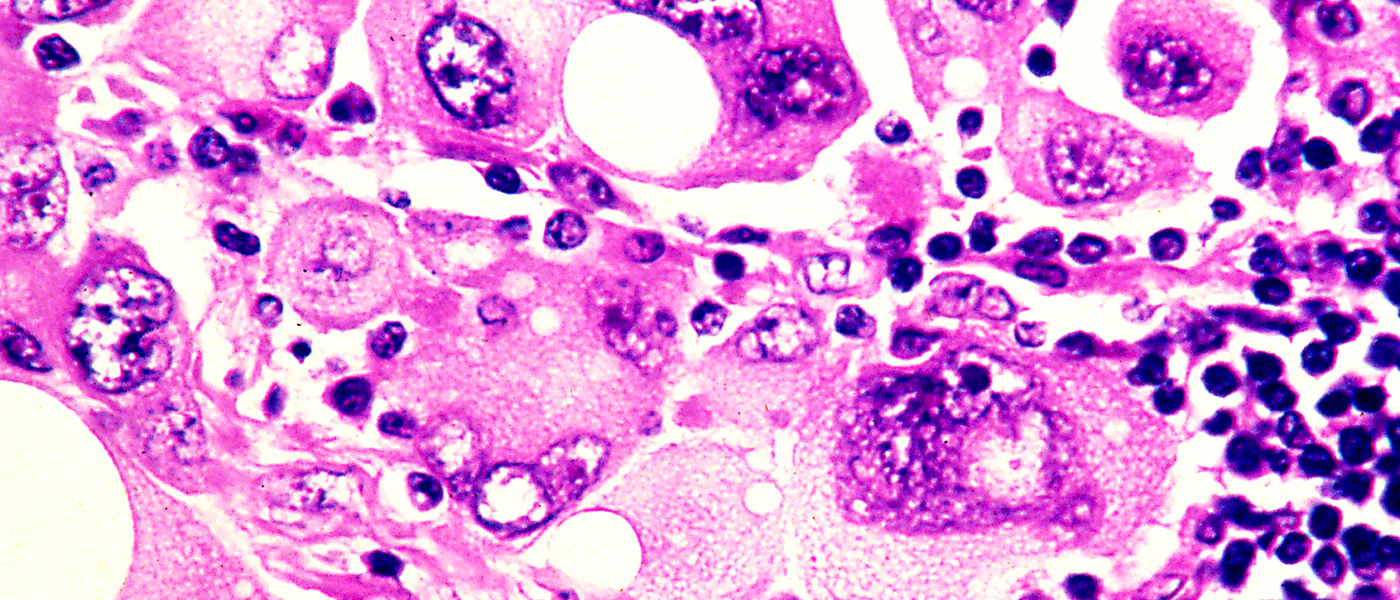

The National Institue for Health and Care Excellence (NICE) recently approved the general use of a combination of two immunotherapy drugs for advanced skin cancer in the National Hearth Service (NHS). This keeps our hopes up that the deadly disease may soon be eradicated or at least stalled.

The use of nivolumab together with ipilimumab was approved by NICE a few months after the combo got its license. According to NICE, patients having advanced melanoma from Wales and England will be the first ones to get it in Europe.

Patients diagnosed with advanced melanoma are usually given a life expectancy of fewer than two years. Thanks to immunotherapy drugs, those who received the first trials got to live for another ten years or so.

The drugs teach the immune system to attack cancer cells but when in combination, the drugs sometimes direct the immune system to attack normal cells as well. This could lead to liver damage and other complications. A trial of the combined drug reported last year got a response of 60% far better than previous responses from just ipilimumab alone.